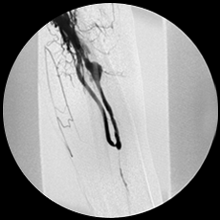

実際の症例②

人工血管静脈吻合部狭窄にて頻回に標準のバルーン拡張(PTA)を繰り返していましたが、ステントグラフト(ゴア社バイアバーン)留置にて狭窄消失しました。

狭窄は消失